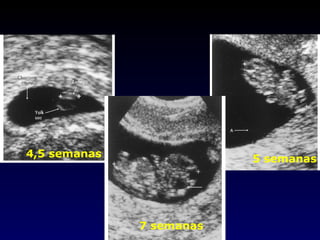

4,5 semanas 5 semanas 7 semanas

4,5 semanas 5semanas 7 semanas